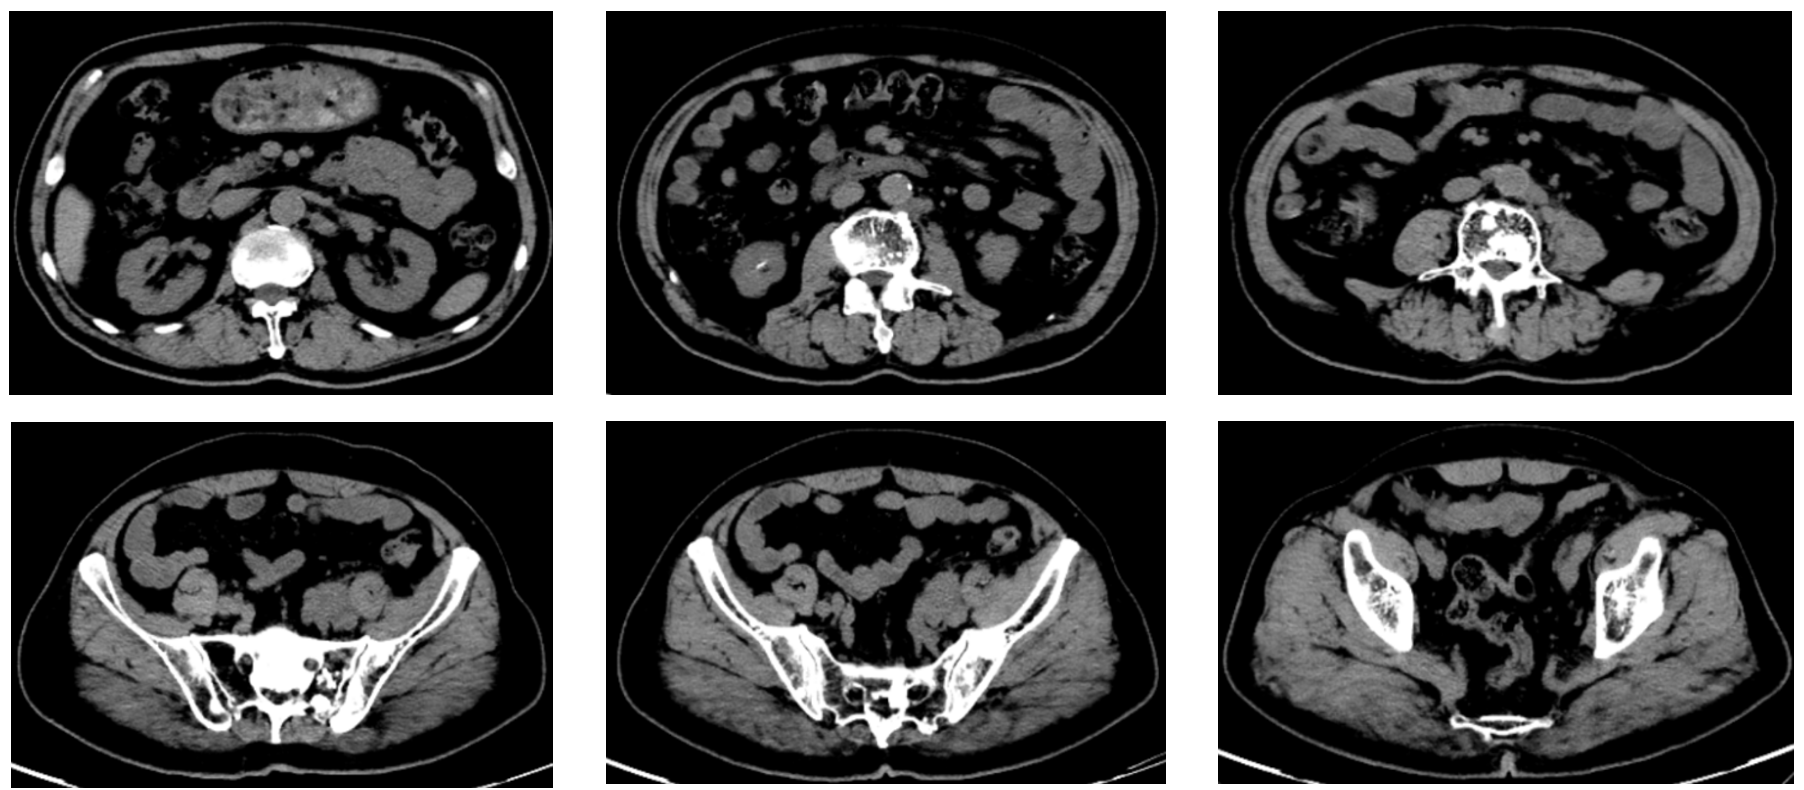

患者一月余前检查时发现右肾肿瘤,伴有肉眼血尿,尿频,尿急,尿痛,伴有腰痛,无发热等其他特殊不适,于当地医院超声检查提示右肾占位性病变,考虑肿瘤,为求进一步诊治于我院就诊,行肾脏增强CT检查提示右肾肿瘤,考虑肾透明细胞癌可能性大,肿瘤突破被膜,肾周受侵。病程中饮食睡眠欠佳,体重减轻近10kg。

右肾肿瘤 9.8cm*7.9cm

肾周受侵

肾门可见肿大淋巴结

未见明显远处转移

右肾肿瘤(肾透明细胞癌可能极大)III期 T3NxM0 IMDC 中危组。

行经腹右肾根切除术治疗。术后病理:透明细胞性肾细胞癌,肿瘤侵犯肾纤维被膜,局部紧邻肾周脂肪几肾盂,未侵犯肾窦脂肪。T3N0M1。

培唑帕尼片800mg,口服,一日一次。

特瑞普利单抗注射液240mg,ivgtt,每两周一次

地舒单抗120mg sc,每28日一次。

放疗计划:右侧肩胛骨、肋骨转移灶 GTV 3600cGy/300cGy/12f。

疗效评估

患者口服培唑帕尼耐受较好,无明显骨髓抑制表现,胆红素正常,但谷氨酰胺转肽酶,谷草转氨酶,碱性磷酸酶仍升高。病灶稳定。